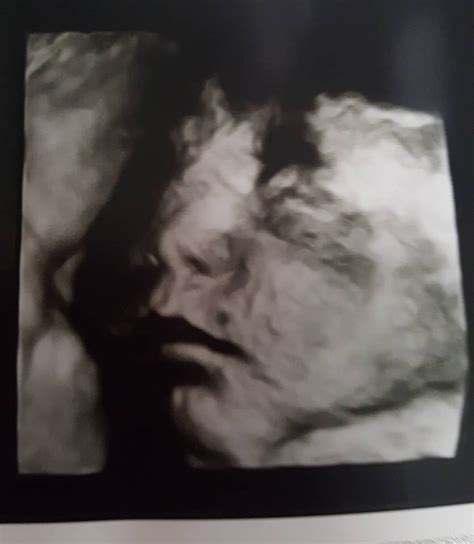

Image Gallery